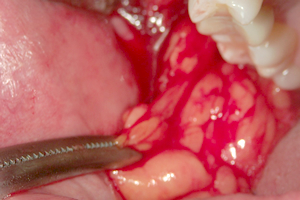

写真で見る「バッカルファットを除去する様子」

② 粘膜剥離

③ バッカルファット

の確認

④ バッカルファット

の露出